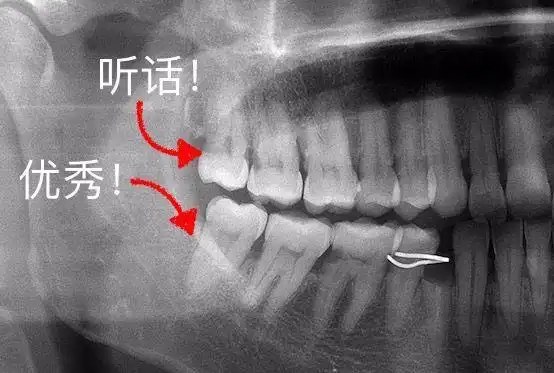

智齿不痛就不用拔吗?看了这篇你就懂了!